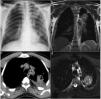

A 59-year-old male patient was admitted to the chest diseases clinic with complaints of sweating, fever and cough. The chest X-ray showed a uniform limited radiopaque area in the upper zone of the left lung. Then, the patient underwent positron emission tomography (PET)/computed tomography (CT) (PET-CT) imaging. In PET-CT, 4×5mm sized hypometabolic cavitary lesion was observed in the left lung upper lobe. Then the patient was asked for thorax tru-cut biopsy due to suspicion of malignancy. We thought that this lesion may be hydatid cyst. Because our city is one of the endemic regions. The patient was taken a contrast thoracic magnetic resonance imaging (MRI). In thoracic MRI, a 45×40×40mm sized T1 weighted imagines hypointense, T2 weighted imagines hyperintense lesion was observed (Fig. 1). There was band formation compatible with germinative membrane in the lesion. Based on these findings, we diagnosed the patient with perforated cyst hydatid. The biopsy was not taken.

(a) Chest X ray PA view showing an ill-defined radiopacity in left upper lung field. (b) T2 weighted imagines haste coronal view hyperintense lesion was observed. There was band formation compatible with germinative membrane in the lesion. (c) Positron emission tomography (PET)/computed tomography (CT) showed hypometabolic cavitary lesion was observed in the left lung upper lobe. (d) T2 weighted imagines haste axial view hyperintense lesion was observed. There was band formation compatible with germinative membrane in the lesion.